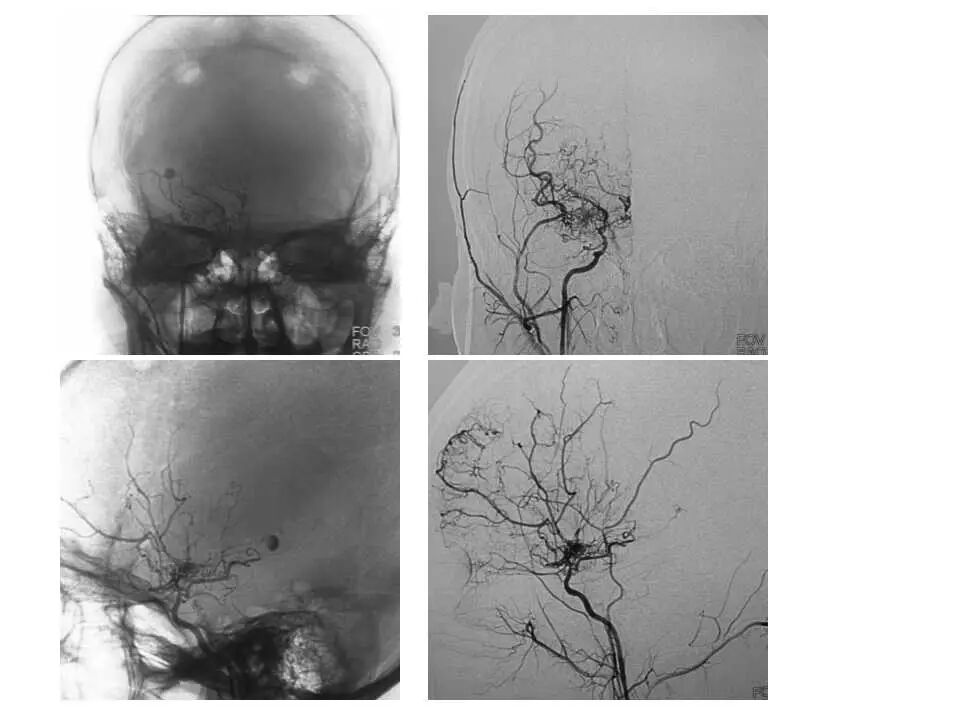

今天为大家分享的是“强生医疗CNV-神经介入专栏”第十五期,由首都医科大学宣武医院何川教授带来的“颅内动脉瘤介入治疗”精彩讲课视频及PPT,欢迎观看、阅读。文章仅代表作者个人观点,如有不同见解,欢迎同道斧正!